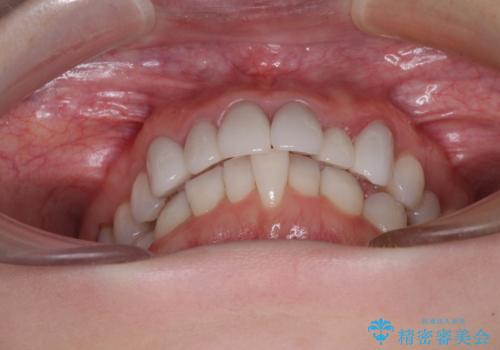

- 全体的なデコボコと、奥歯の欠損を放置した結果倒れ込んだ奥歯などを気にして来院された患者様です。

ワイヤー矯正の方が理想的な仕上がりとできる状態でしたが、上顎前歯にクラウンが装着されているため、インビザラインにて矯正治療を行うこととしました。

インビザラインのみで対応できないときにはワイヤー矯正を併用することとし、矯正治療後にはオールセラミッククラウンによる補綴治療を行うこととしました。